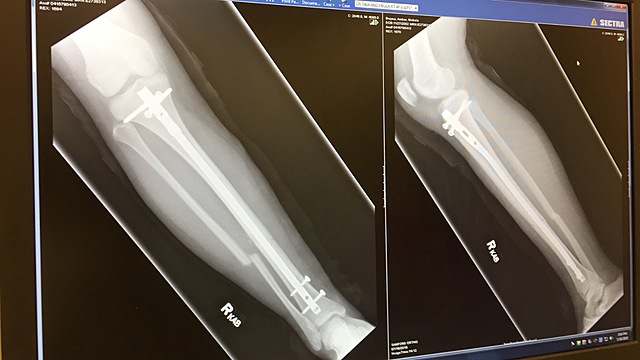

We went in for a check up on how my leg was doing and by the x-ray my leg had gotten worse. The cast wasn't doing my leg any good so the doctor said I had no choice but to get surgery.

When I got surgery i was put in a splint and my leg felt very heavy because I had metal in my bones.